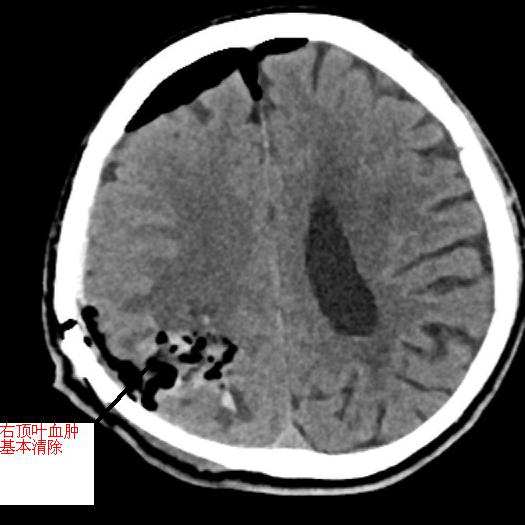

黃阿伯,現(xiàn)年60歲,9月中旬被發(fā)現(xiàn)躺于地上,言語(yǔ)不能、反應(yīng)遲鈍、左側(cè)肢體無(wú)力,緊急送至我院急診科,考慮右頂葉出血破入腦室,出血量超90ml,出血量大,周圍腦溝腦回、右側(cè)腦室受壓,呈嗜睡狀態(tài),有急診手術(shù)指征。不進(jìn)行手術(shù)后續(xù)水腫出現(xiàn)及加重、顱內(nèi)壓力增加、占位效應(yīng)加重,將進(jìn)一步損害腦組織。

術(shù)中,見手術(shù)視野壓力高,腦組織受壓,黃金鐘主任給予內(nèi)鏡下充分清除血腫、止血,見腦組織壓力減低,腦血管搏動(dòng)有力。

▲左圖為術(shù)前顱內(nèi)血腫,右圖為手術(shù)后原血腫位置,血腫已基本清除

術(shù)后,黃阿伯無(wú)需特殊設(shè)備維持,神志漸清。隨后,經(jīng)康復(fù)治療,神志清楚,對(duì)答配合,左側(cè)肢體肌力較前恢復(fù)。10月初好轉(zhuǎn)后順利出院,囑居家繼續(xù)康復(fù)鍛煉。